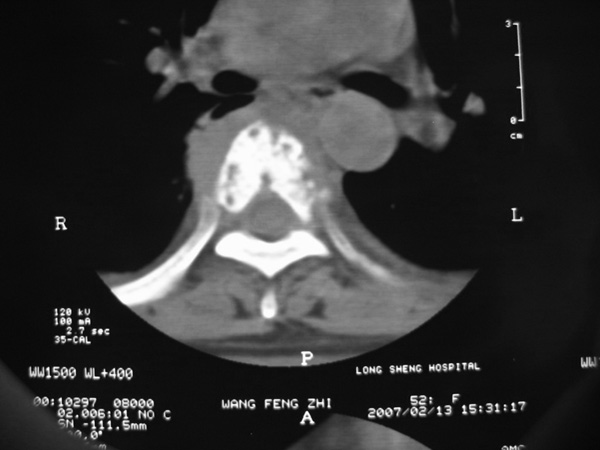

女,45岁,胸背部疼痛2个月。t6、7胸椎病变。

椎旁肿胀的软组织内可见气泡影,对脊柱的化脓性和结核性的鉴别有帮助吗?

胸椎结核与脊柱椎体化脓性脊柱炎,从影像特点很难鉴别,本例具有二者的共性特点,建议结合临床鉴别以下,我考虑:1 化脓性脊柱炎.2 胸椎结核.原因:1 椎旁脓肿内含气泡.2 椎体溶骨性破坏,但未见死骨.

胸椎体骨质破坏伴死骨形成,椎周环状软组织肿胀,范围较长,考虑胸椎结核伴冷脓肿形成。鉴别;1转移性肿瘤;椎弓根骨质破坏多见,软组织肿块局限。椎间隙尚存。有原发肿瘤病史。2,淋巴瘤;骨质破坏 然骨皮质轮廓线尚存,当椎管骨示环状软组织影时有一定特异性。病变较局限。建议mri增强,观察冷脓肿与软组织肿块很有帮助。